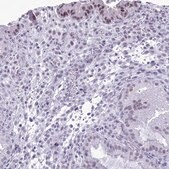

HPA044350

Anti-DHX40 antibody produced in rabbit

IF, IHC

immunofluorescence: 0.25-2 μg/mL, immunohistochemistry: 1:200-1:500

• IHC tissue array of 44 normal human tissues and 20 of the most common cancer type tissues.